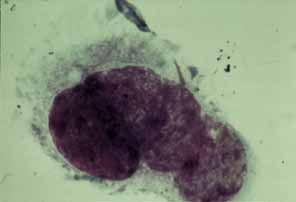

serologies. Cytology of cutaneous vesicular scrapings with Papanicolaou's stain

displays multiple eosinophilic intranuclear inclusions, the so-called

Lipschütz type II bodies (Fig. 21). In addition, multinucleated giant cells identical to those of herpes

simplex virus infection can be seen. Although the inclusions cannot

be seen with either Giemsa or Gram's stain, the giant cells are

readily visible with Giemsa stain (Tzanck preparation).50 The spherical icosahedral proteinaceous coat (capsid) of the

VZV can be seen with electron microscopy, although it is impossible to

distinguish VZV from other members of the herpesvirus group unless it

is previously tagged with specific peroxidase-labeled antibody.50  Fig. 21 Herpes zoster ophthalmicus (HZO): scraping of vesicle. Multinucleated

giant epithelial cell with intracytoplasmic basophilic inclusions, so-called

Lipschutz type II bodies (Giemsa stain, Tzanck

preparation). Fig. 21 Herpes zoster ophthalmicus (HZO): scraping of vesicle. Multinucleated

giant epithelial cell with intracytoplasmic basophilic inclusions, so-called

Lipschutz type II bodies (Giemsa stain, Tzanck

preparation).